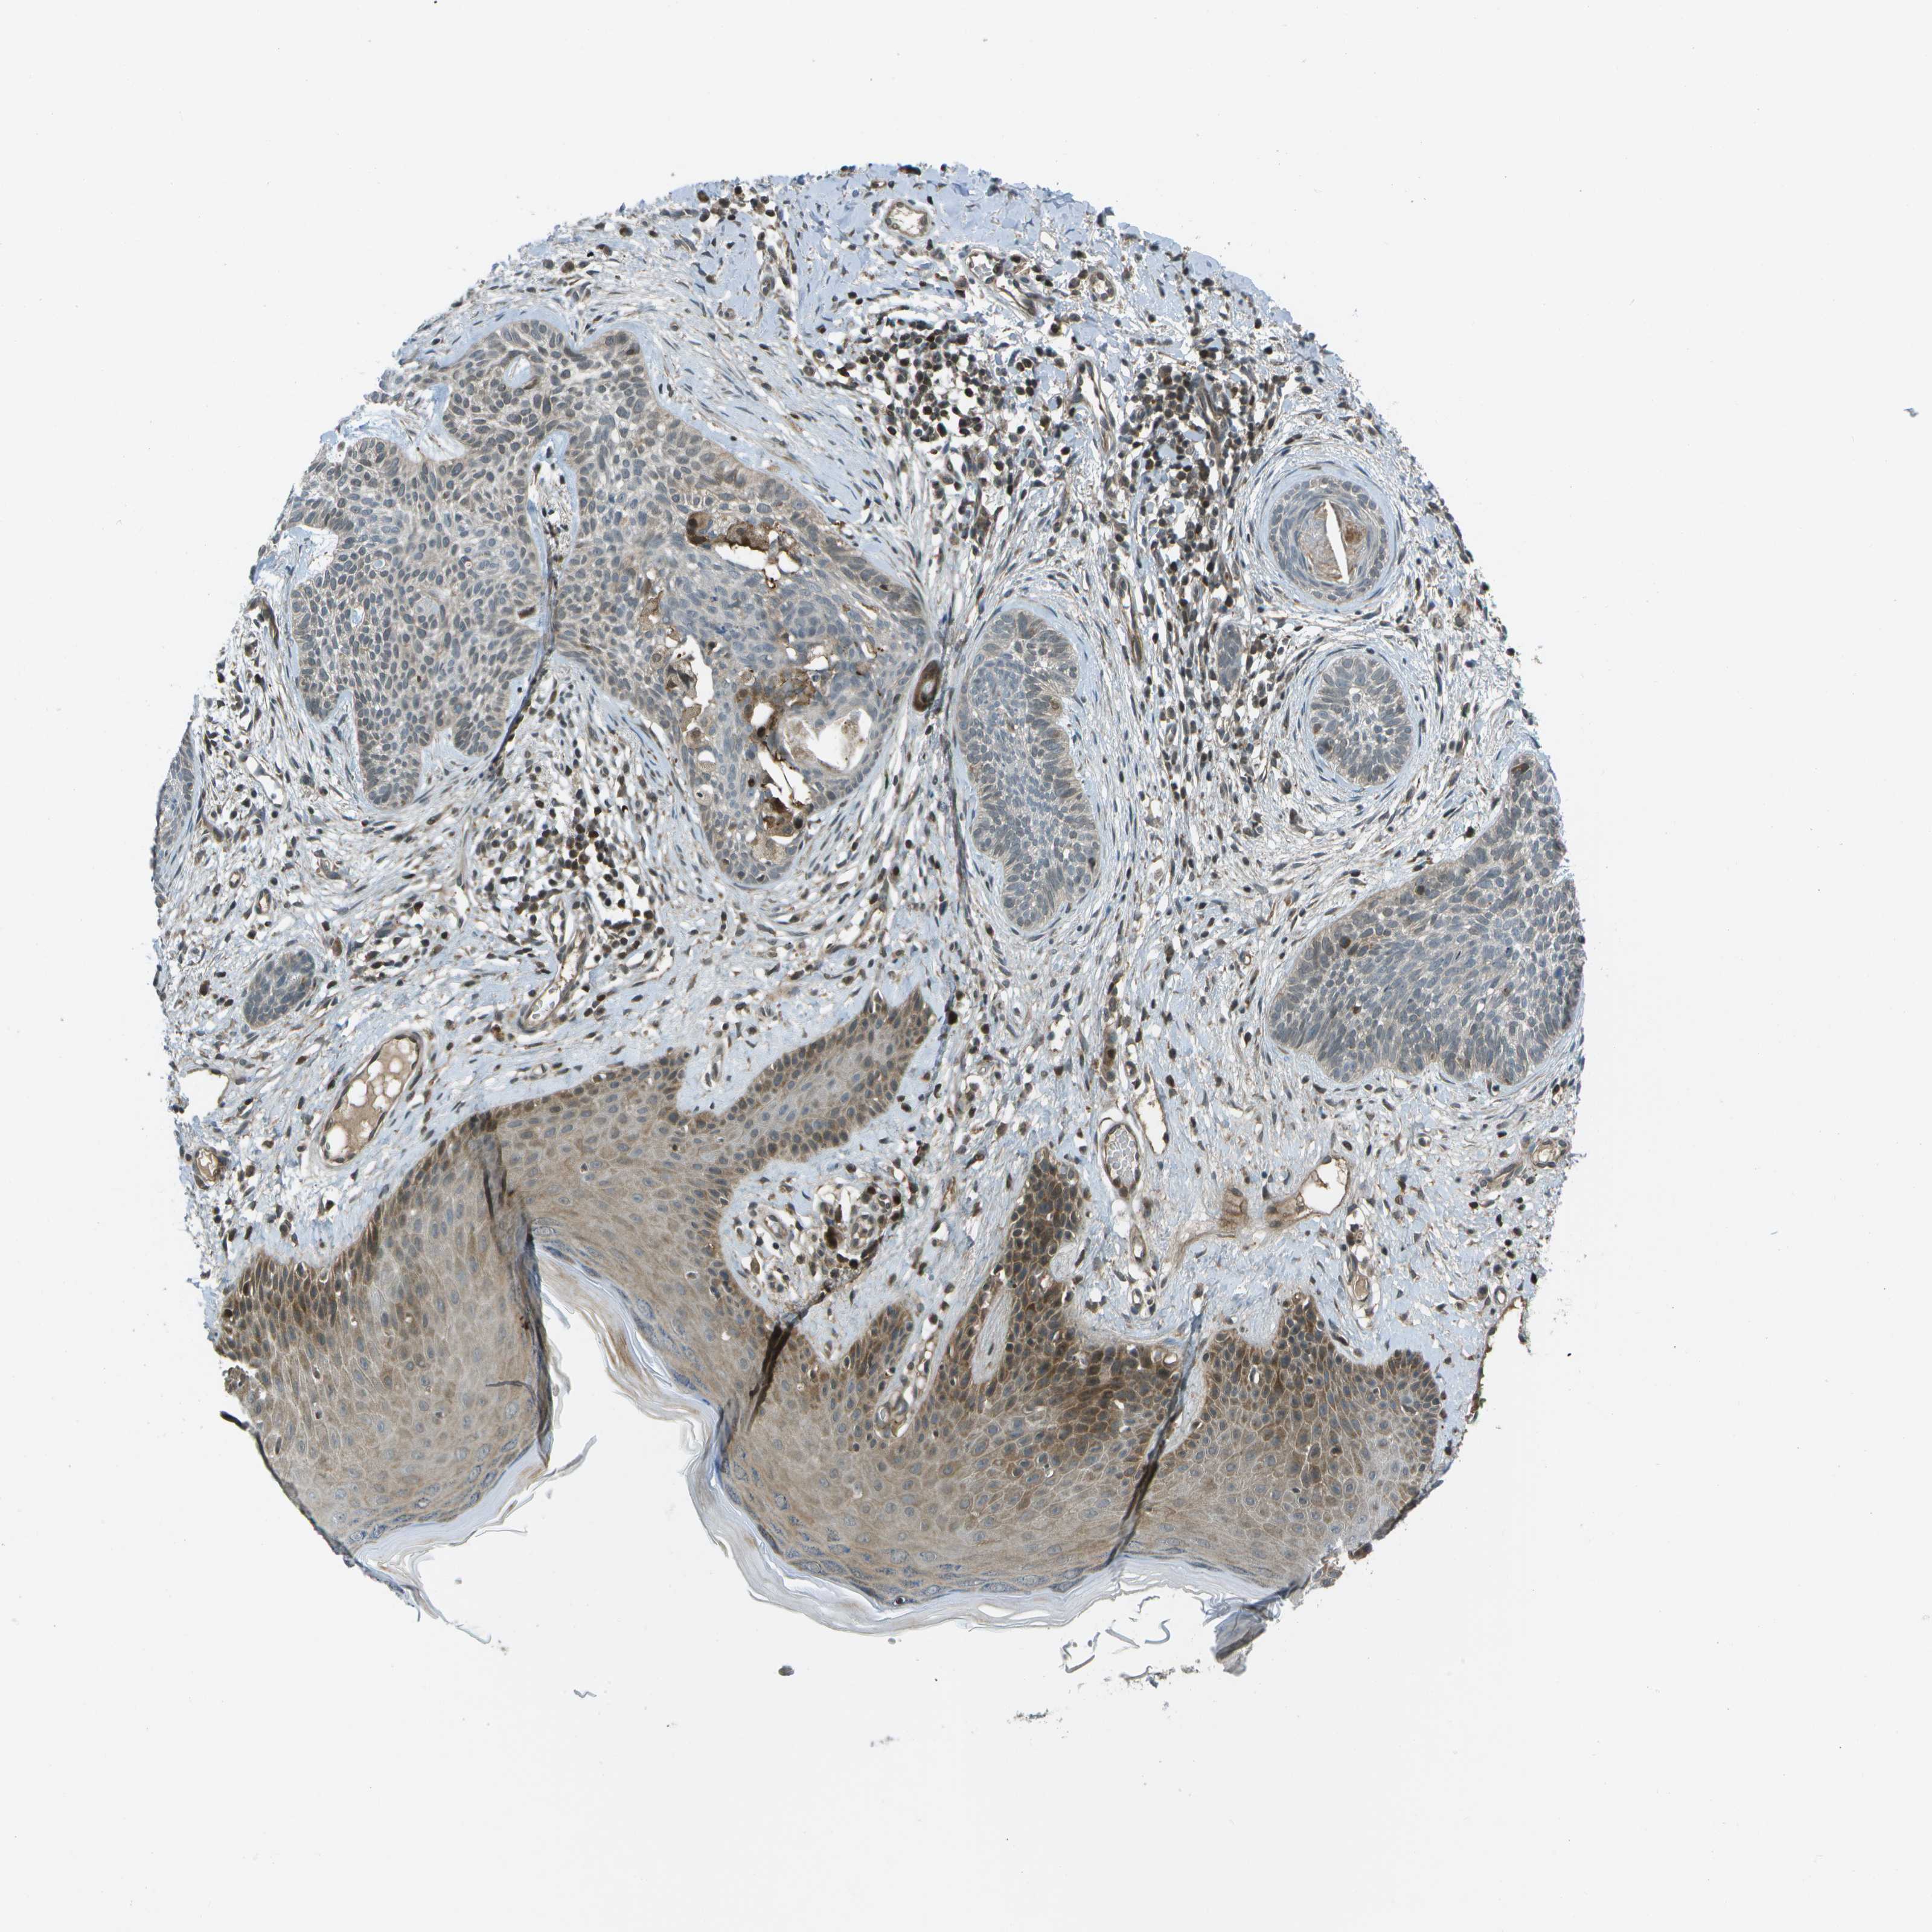

SKIN CANCER - Protein expressioni

A mouse-over function shows sample information and annotation data. Click on an image to view it in a full screen mode. Samples can be filtered based on level of antibody staining by selecting one or several of the following categories: high, medium, low and not detected. The assay and annotation is described here.

Each image is clickable and will lead to virtual microscopy that enables deeper exploration of all samples and also displays staining intensity scores, fraction scores and subcellular localization as well as patient and tissue information for each sample.

Antibody HPA016830

Staining

High

Intensity

Strong

Quantity

>75%

Location

Nuclear

Squamous cell carcinoma in situ, NOS

Squamous cell carcinoma, NOS

Squamous cell carcinoma, metastatic, NOS

Basal cell carcinoma

Adnexal tumor, benign